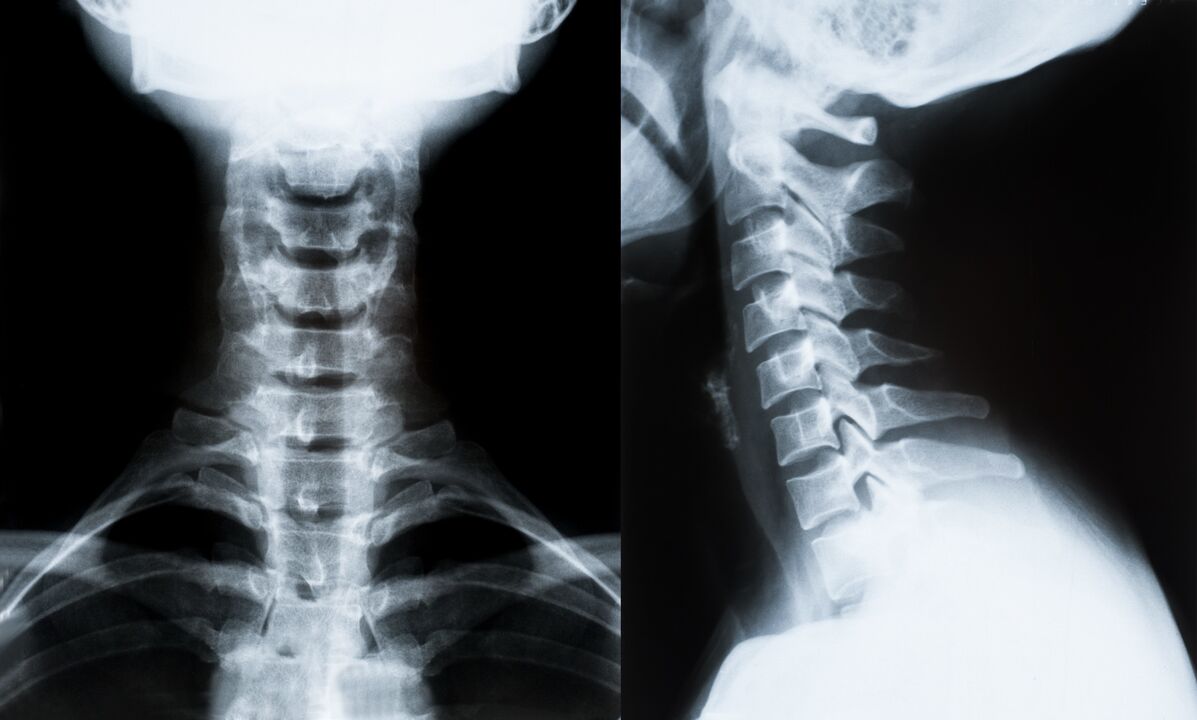

Glavne metode diagnoze in nadaljnjega določanja zdravljenja osteohondroze vratne hrbtenice:

- Rentgensko slikanje. Najmanj učinkovita, a tradicionalna diagnostična metoda.

- Slikanje z magnetno resonanco je najučinkovitejša diagnostična metoda. Pri tovrstnem pregledu pacienta so vidne vse potrebne strukture.

- Če je treba spremembe izmeriti, uporabimo računalniško tomografijo. Ugotavlja prisotnost kile in drugih stvari.

- Zadnja metoda je ultrazvočno dupleksno skeniranje. Ta raziskovalna metoda določa hitrost pretoka krvi v arterijah.

Nemogoče je natančno določiti bolezen hrbtenice doma.